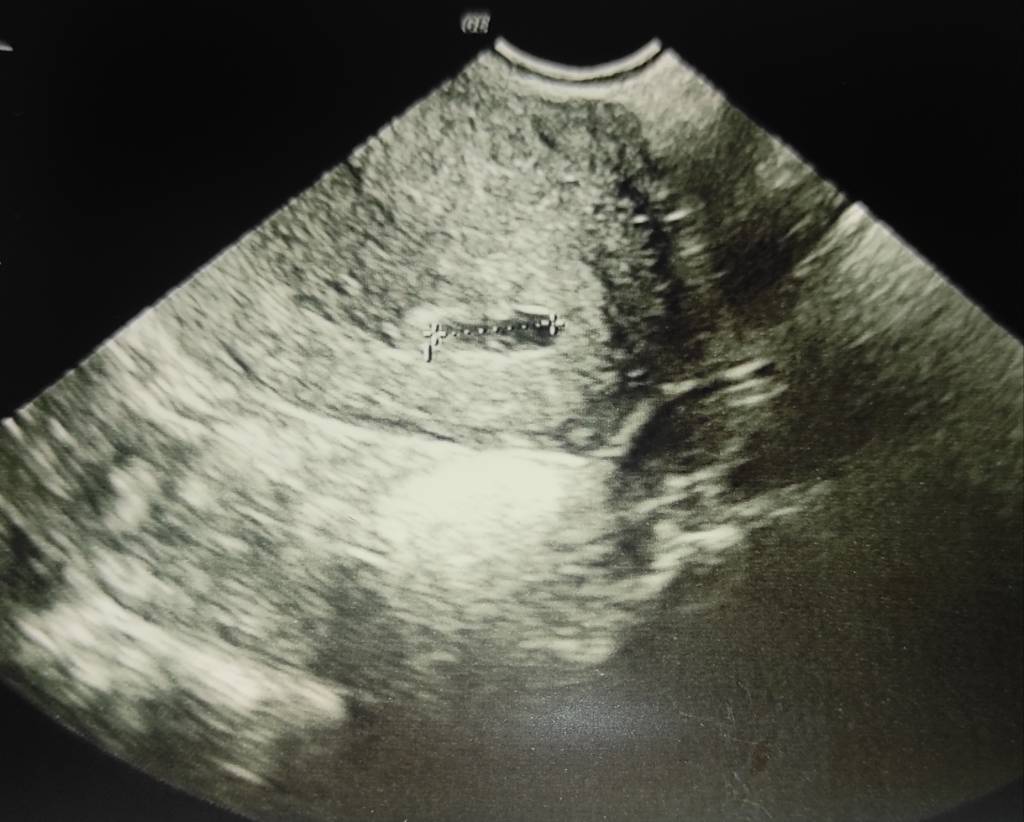

@marina7 jak masz zaufanie do swojego lekarza to ja bym na spokojnie poczekała do kolejnej wizyty. Nie za dużo na tym etapie da się zrobić. Jeżeli to jakiś nowy lekarz to poszłabym gdzieś indziej skonsultować bo betę masz bardzo wysoką i tydzień też taki że pęcherzyk powinien być, choć różnie bywa tak jak dziewczyny piszą. Opcje są różne, może się okazać że za tydzień zobaczysz śliczny pęcherzyk.

Właśnie lekarz coś znalazł ale nie do końca jest pewny czy jest po pęcherzyk ciążowy czy coś innego.

Załączniki

• IMG_20201105_214140.jpeg

IMG_20201105_214140.jpeg

78,9 KB · Wyświetleń: 198